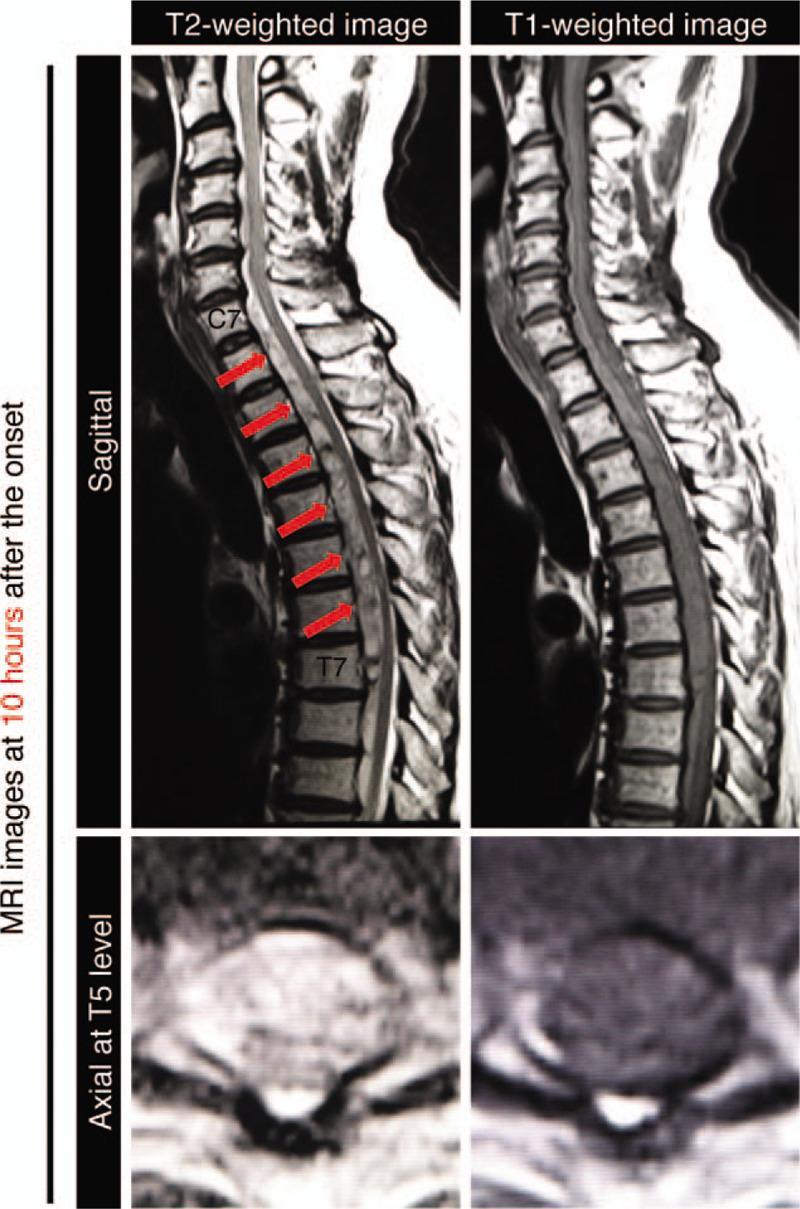

A 59-year-old male presented with sudden severe back pain and rapid onset of paraplegia. This symptom had continued developing while he was transferred to the emergency department. Initial physical examination showed flaccid paralysis of both lower limbs with areflexia and loss of all sensation below T6 bilaterally. MRI images showed an anterior subdural hematoma from C7 to T7 with spinal cord compression.

一名59岁男性突发严重背痛并迅速出现截瘫。在转至急诊科的过程中,该症状持续发展。初始体格检查显示双下肢弛缓性瘫痪,无反射,双侧T6以下所有感觉丧失。MRI图像显示C7至T7水平硬膜下血肿并伴有脊髓受压。